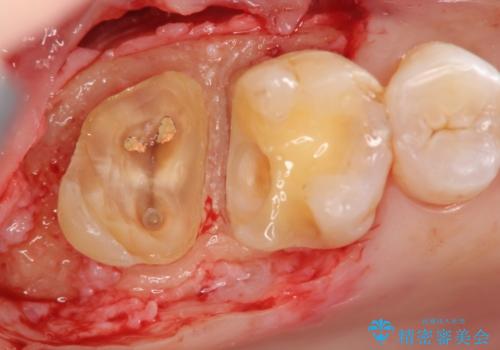

歯髄方向 歯肉方向へと深い 2種類の大きな虫歯

- 他院で虫歯が大きすぎて歯を抜くしかないと言われ、歯を残す手段はないものかと当院へ初診来院されました。

#17は失活歯で歯肉方向への縁下カリエス、#16は生活歯であるものの歯髄ギリギリの処置となるであろうとが予想される治療です。

歯周外科、マイクロスコープを用いた虫歯治療を行い歯を残す治療計画を立てます。

- 30万円(仮歯・ファイバーコア・ジルコニアクラウン・歯周外科・セラミックインレー)費用は治療当時の料金となります

深い虫歯には歯周外科、マイクロスコープを用いた丁寧な虫歯の除去を行うことで歯の神経や歯そのものを残すことが可能になります。